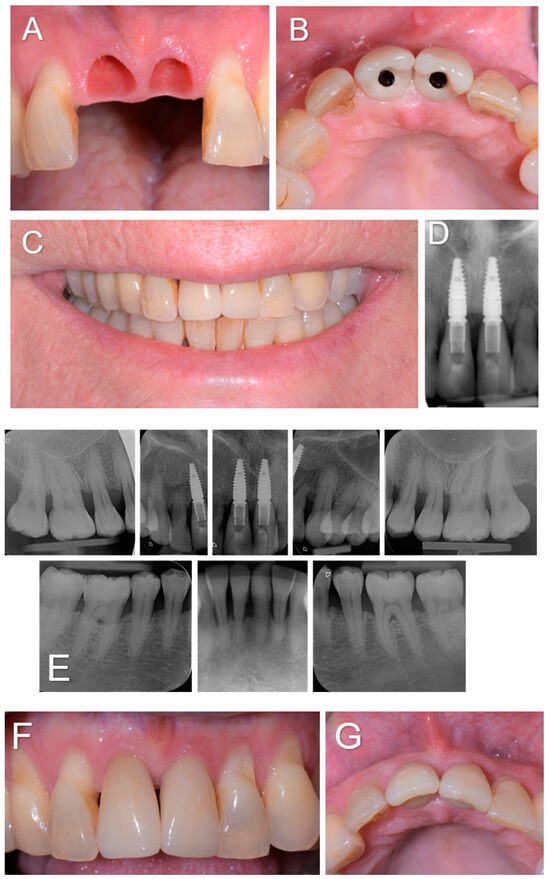

A 61-year-old woman was referred to the Oral Surgery and Implantology Unit of the University Hospitals of Geneva for the treatment of edentulous sites after the dental avulsions of teeth 11 and 21 following traumatic shock due to endotracheal intubation under general anesthesia performed to remove a laryngeal cyst. Past medical history was significant for pharyngeal dysesthesia and a supraglottic cyst. The dental history revealed that the patient had a history of chronic generalized periodontitis treated a few years earlier. Clinical and radiological examination showed generalized bone loss, especially at the edentulous sockets 11 and 21 and adjacent teeth 12 and 22 (Figure 1).

Figure 1.

Clinical view (A) and intra-oral radiographs (B) showing the initial clinical status after dental avulsions due to endotracheal intubation as well as the severe chronic periodontal disease.

Figure 3.

(A–D). Soft tissue condition when the two screw-retained single-unit crowns (E-max. press) were delivered 3 months post-operatively (A,B), and the clinical and radiographic examinations at the 3-year follow-up (C–G).